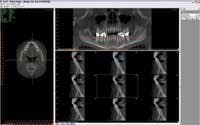

The Pankey Institute has advanced its digital-imaging capabilities with the acquisition of a 3-D Cone Beam Imaging System. This system produces thorough, three-dimensional views of all oral and maxillofacial structures, allowing enhanced diagnosis and treatment planning. The images are more easily acquired with improved accuracy than images produced by more traditional panorex and transcranial radiograph technology.

Here’s how it works. Patients are seated in an open environment. The machine, which resembles a traditional panorex, captures the natural orientation of the anatomy. The compact design and rapid image-acquisition capabilities enable the dental CT scan to capture 3-D images within 20 seconds. Data transfer to a local computer takes less than a minute. The completed scan is displayed on the monitor, and the interactive software allows the image to be formatted easily and the desired “slices” to be selected for immediate viewing.

Of particular interest is the ability to image the articular eminence and condylar anatomy, and then isolate images specific to the medial or lateral pole of the condyle. Users may export data to a variety of implant treatment planning and 3-D viewing software programs. This software provides immediate, 3-D digital reconstructions of a patient’s mouth, face, and jaw areas, which can be viewed on a computer screen or printed in full color.